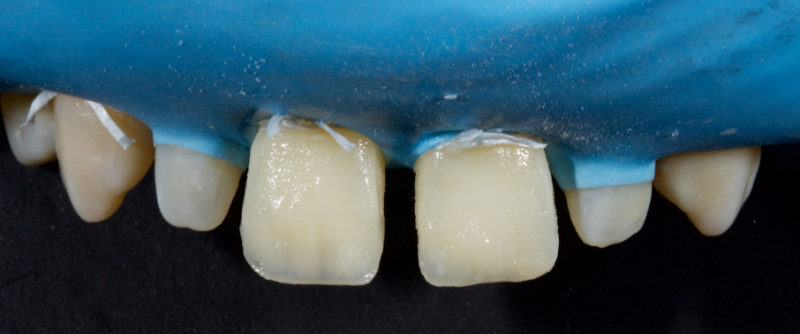

The anterior teeth had lost around 25% of the coronal structure, and dentin was exposed (Figs. 1–3). The patient requested a minimally invasive solution.

After deprogramming with a splint and occlusal equilibration, the anterior teeth were restored with direct composite resin using a minimal prep approach (Figs. 4 and 5). The occlusal scheme was idealized (Fig. 6).

Inferiorly, the dentin resin mass should not be placed apical to the superior aspect of the infinity bevel since that would result in a visible opaque line in the final restoration. The dentin mass should be under contoured (Figs. 14 and 15).